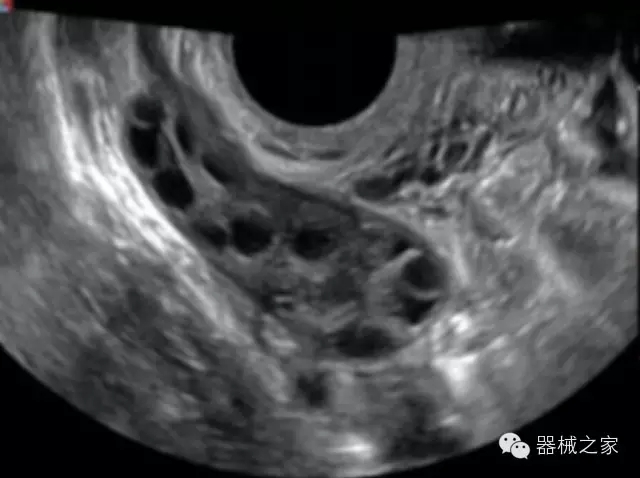

品牌:開立(SONOSCAPE)

公司簡介:

深圳開立生物醫(yī)療科技股份有限公司作為中國民族醫(yī)療產(chǎn)業(yè)的優(yōu)秀引導(dǎo)者,自成立伊始,一直致力于臨床醫(yī)療設(shè)備的研發(fā)和制造,產(chǎn)品涵蓋醫(yī)用數(shù)字超聲診斷系統(tǒng)、電子內(nèi)窺鏡系統(tǒng)、全自動五分類血液細(xì)胞分析儀以及自主研發(fā)的探頭群。

官方網(wǎng)站:www.sonoscape.com.cn

經(jīng)典產(chǎn)品:S8EXP

臨床圖片賞析

產(chǎn)品特點

優(yōu)異的成像技術(shù)

·亞陣元技術(shù):獨有的亞陣元技術(shù),對獨立晶片做二次切割,減少旁瓣偽像,增加臨床診斷的準(zhǔn)確性;

·μ-Scan微米成像技術(shù):開立獨有的μ-Scan技術(shù),還原出真實細(xì)膩、層次對比優(yōu)異的二維圖像;

·倒相諧波成像技術(shù):倒相諧波技術(shù)在去除基波信號的基礎(chǔ)上獲取兩倍二次諧波信號,提高組織圖像的對比分辨力;

·智能微血流成像技術(shù):智能微血流捕捉技術(shù)可以提取出隱藏在背景噪聲中的弱血流信號,大大提高低速血流的敏感性;

全面的臨床解決方案

超聲科常規(guī)領(lǐng)域應(yīng)用

·移植S40高端臺式彩超高端平臺技術(shù),滿足超聲科腹部、淺表、婦產(chǎn)科、心血管、肌骨等應(yīng)用,提供超聲科完美解決方案;

·實時的彈性成像技術(shù):提高了小器管(乳腺,甲狀腺、淺表軟組織腫瘤等)疾病鑒別診斷;

·IMT血管內(nèi)中膜自動測量:為血管性疾病評估提供了有效的評估手段;

·心功能綜合指數(shù)(TEI指數(shù)):用于左、右心室整體心臟收縮舒張功能評估的測量方法;

·全方位可調(diào)M型:有利于更好的觀察心腔大小及室壁階段性運動的異常情況;

·組織多普勒成像(TDI):TDI可定量評價心肌運動,判斷是否有局部病變,還可評價早期的舒張功能;

·高效3D/4D成像技術(shù):高速的4D幀頻,豐富的3D成像模式,智能斷層切片功能;

POC領(lǐng)域解決方案

·外觀小巧;

·穿刺增強技術(shù):可有效提高進(jìn)針區(qū)圖像分辨率,提高進(jìn)針亮度,全面提高一次性穿刺的成功率;

全面的術(shù)中探頭解決方案

·小凸探頭:開放性手術(shù),實時監(jiān)測病灶位置,提高手術(shù)成功率,可應(yīng)用于麻醉科、肝膽外科、腫瘤外科、神經(jīng)外科、泌尿外科等手術(shù);

·L型線陣探頭:高分辨率圖像,清晰顯示病灶位置,提高手術(shù)成功率,可應(yīng)用于麻醉科、胸外科、肝膽外科、腫瘤外科、神經(jīng)外科、泌尿外科等應(yīng)用;

·MPTEE:經(jīng)食道探頭術(shù)中監(jiān)測,可測量心臟前負(fù)荷(左室舒張末期大小、右房大小)、心排血量、后負(fù)荷、收縮功能、室壁運動分析、肝靜脈血流(與中心靜脈壓相關(guān))等,術(shù)后還能及時評估手術(shù)效果評估;

·獨有的大角度及實時溫控技術(shù),能同一切面顯示宮頸及宮體,有效減低了患者的痛苦,及保護(hù)粘膜保證了醫(yī)療安全;

高效的人機工程學(xué)設(shè)計

·15‘’高清醫(yī)用顯示器;

·內(nèi)置雙探頭接口;

·可升降臺車,1拖3探頭擴展器;

·m-Tuning一鍵優(yōu)化;

CFDA注冊證編號

·粵食藥監(jiān)械(準(zhǔn))字20132230491